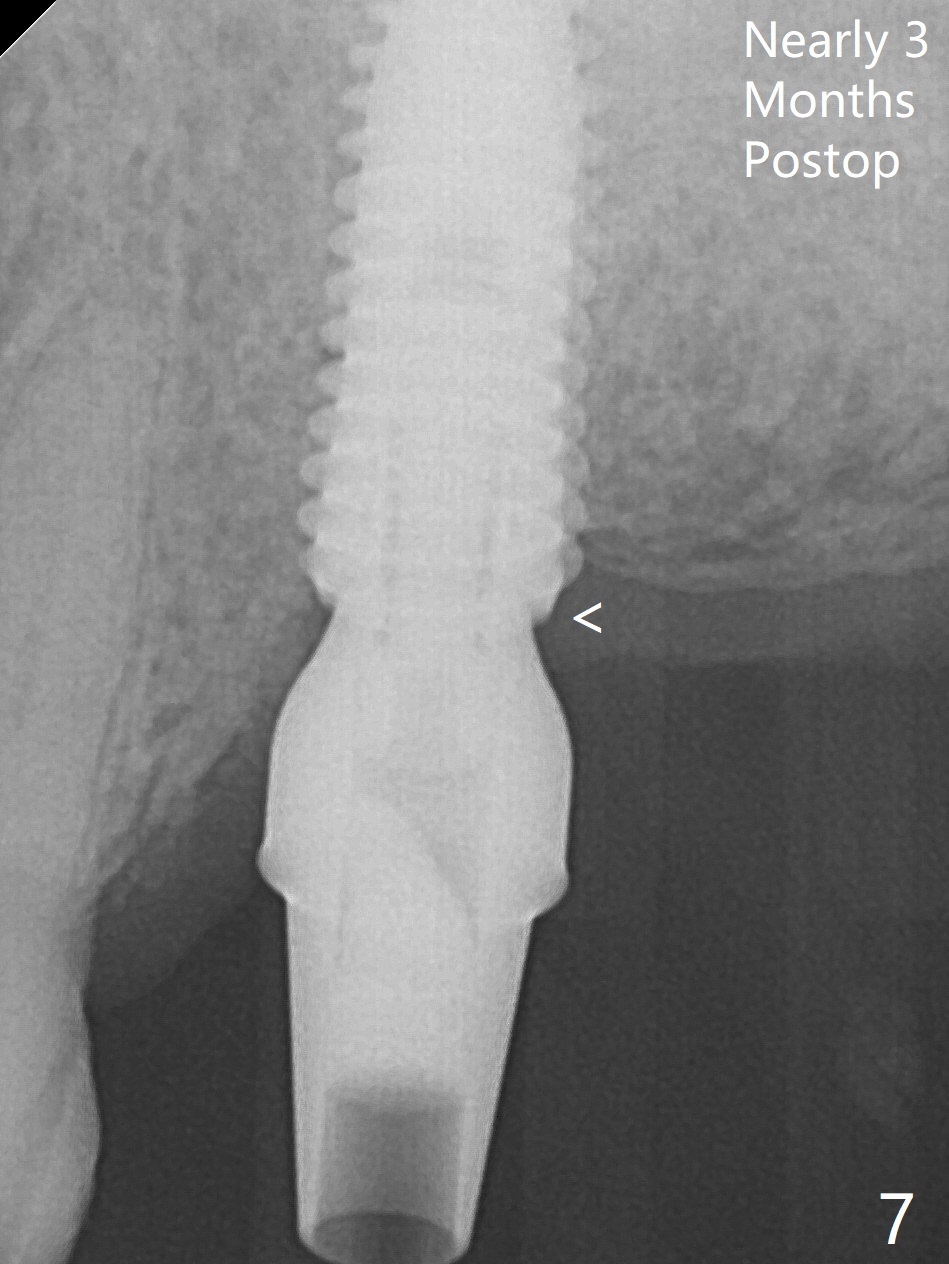

The septum is found to be pointed after extraction of the tooth #14 (Fig.1 *). The septum is flattened with Rongeur (Fig.2 *) prior to osteotomy. Because of interference of the mesial bone (Fig.3 *), osteotomy does not reach the depth with use of stopper. Without the latter, a 5x11.5 mm implant barely penetrates the sinus floor (Fig.4 (no postop nasal hemorrhage)). Also due to the mesial bone interference, a 6.5 mm abutment is not seated. Finally a 5.5x7(5) mm abutment is placed for an immediate provisional. Periodontal dressing is applied to cover the buccal repaired gingiva (Fig.5 *). There is minimal thread exposure after removal of the provisional nearly 2 months postop (Fig.6). The provisional does not return for easy self cleansing. In fact this is not an easy task, because of the posterior position (Fig.8 (after Piezo scaling)). The distal implant remains exposed; the abutment is removed and a healing screw is placed (Fig.9). The implant should have been subcrestal distally (Fig.7 <, nearly 3 months postop). One month later, the implant seems to be buried (Fig.10). The straight abutment is changed to an angled one (4.5 x15 degree A (5) mm) before impression retake (Fig.11,12 (<, dashed line: access hole)). The implant should have been placed more mesial (Fig.13). Surgical guide is needed. There is no implant exposure clinically or in CBCT sections 1 year 2 months post cementaton (Fig.14), although 3 D image suggests missing distopalatal plate (Fig.15).